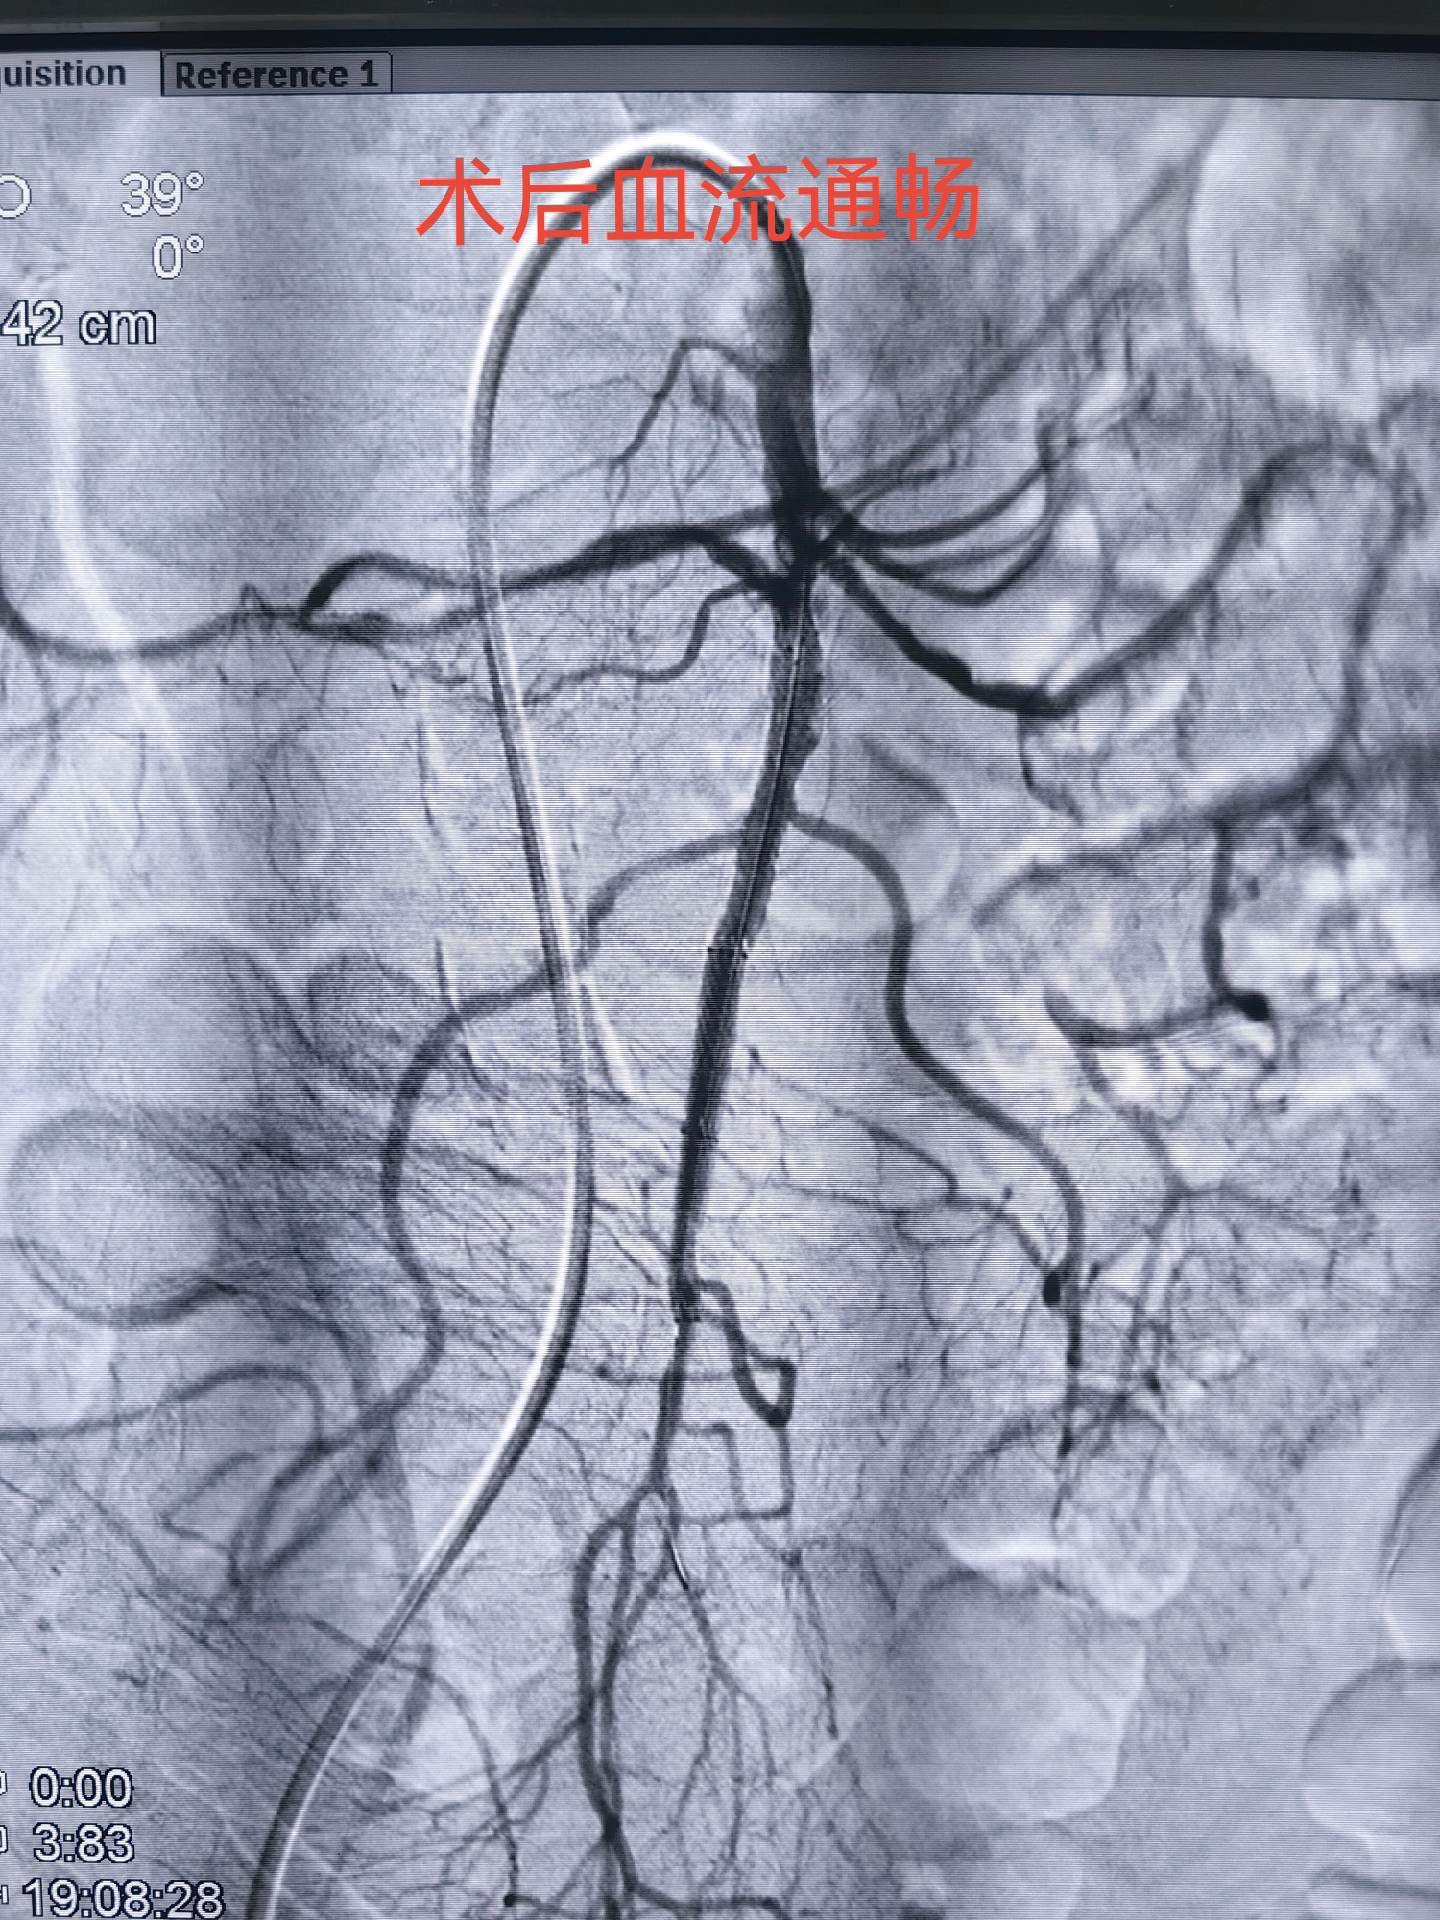

肠系膜上动脉栓塞,会导致肠缺血坏死危及生命,急诊介入开通挽救